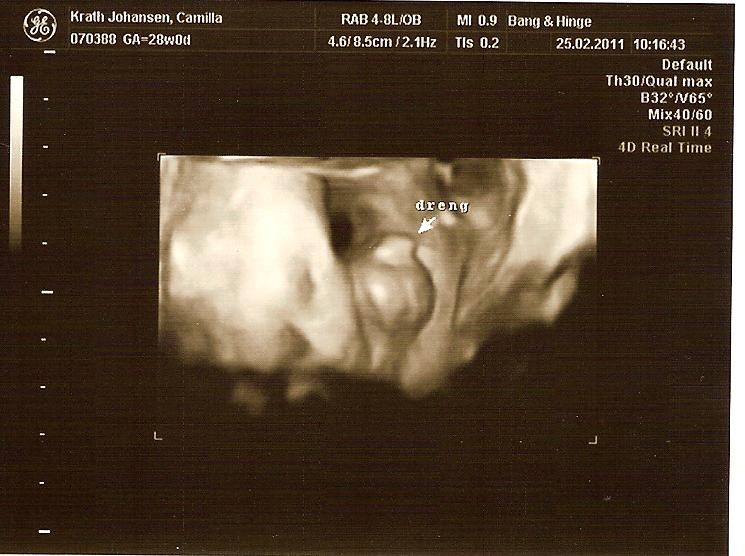

Selvom vores søn var lille, så havde han ikke meget plads at ligge på i uge 30, og da de ligger "lidt klemt", så blir det sværere at se noget, jeg større de blir. Vi fik nogen rigtig gode billeder, men det tog en del tid, fordi hans arme lå presset op foran hans ansigt og det er jo svært lige at flytte dem

Men sikke en stor oplevelse